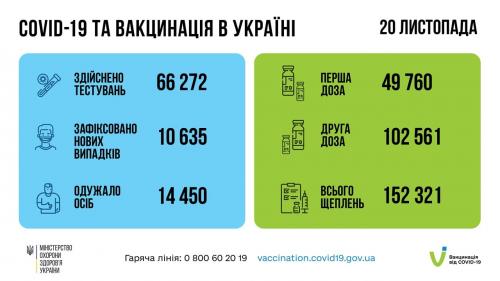

МОЗ: Уперше з початку пандемії було зроблено понад 100 тисяч ПЛР-досліджень за добу